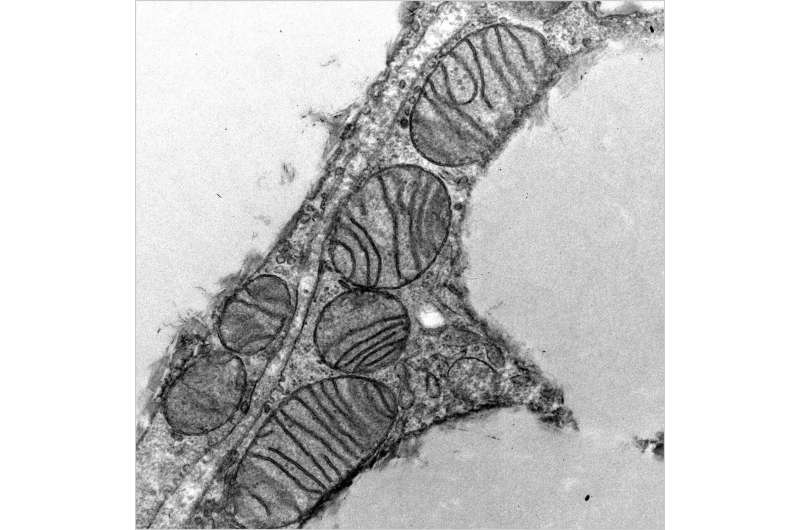

В новом исследовании был обнаружен микропротеин под названием SLC35A4-MP, который играет ключевую роль в поддержании структуры митохондрий и регулировании метаболического стресса в жировых клетках мышей. Полученные данные открывают путь для разработки новых методов лечения на основе микропротеинов для борьбы с ожирением, старением и другими митохондриальными нарушениями.

«Микропротеины долгое время считались случайным генетическим мусором, но наша работа подтверждает растущее количество исследований, показывающих, что многие из них являются важными регуляторами клеточной физиологии, – отмечает Алан Сагателян, профессор Института Солка. – В данном исследовании мы показываем, что микропротеин отвечает за поддержание структуры и функции митохондрий в бурой жировой ткани, которая регулирует температуру тела и энергетический баланс».